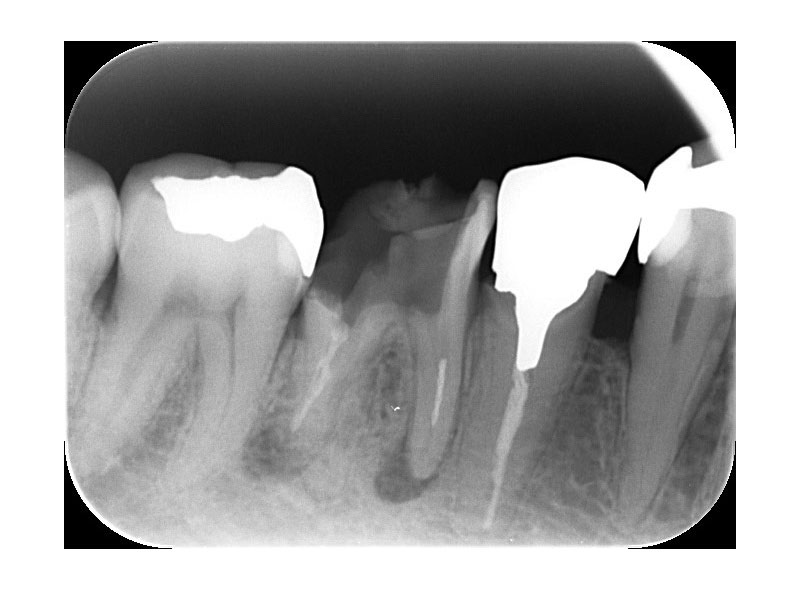

● ① 骨が溶けてしまう

根の先の炎症が続くと、

周囲の骨が ジワジワと吸収(溶ける) していきます。

レントゲンで丸く黒く写るのがそのサイン。